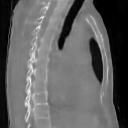

The results presented in Table 1 and 2 show our proposed method’s performance on unconditional 3D brain MR and chest CT image generation. Our proposed approach not only outperforms most comparing methods in FID and MS-SSIM metrics, it also has the lowest inference GPU memory footprint at a resolution of and was the only diffusion-based method that could be trained at a resolution of . Operating in the wavelet domain and profiting from the reduced spatial dimension also results in a relatively short inference time of / at the respective resolutions. Compared to the results presented in [23], we did not find that incorporating wavelet information into the network’s feature space (WavU-Net) increased the model’s performance. Qualitative results of our proposed method (WDM) are shown in Fig. 2 and 3. A qualitative comparison of samples produced by all evaluated methods can be found in the Supplementary Material.